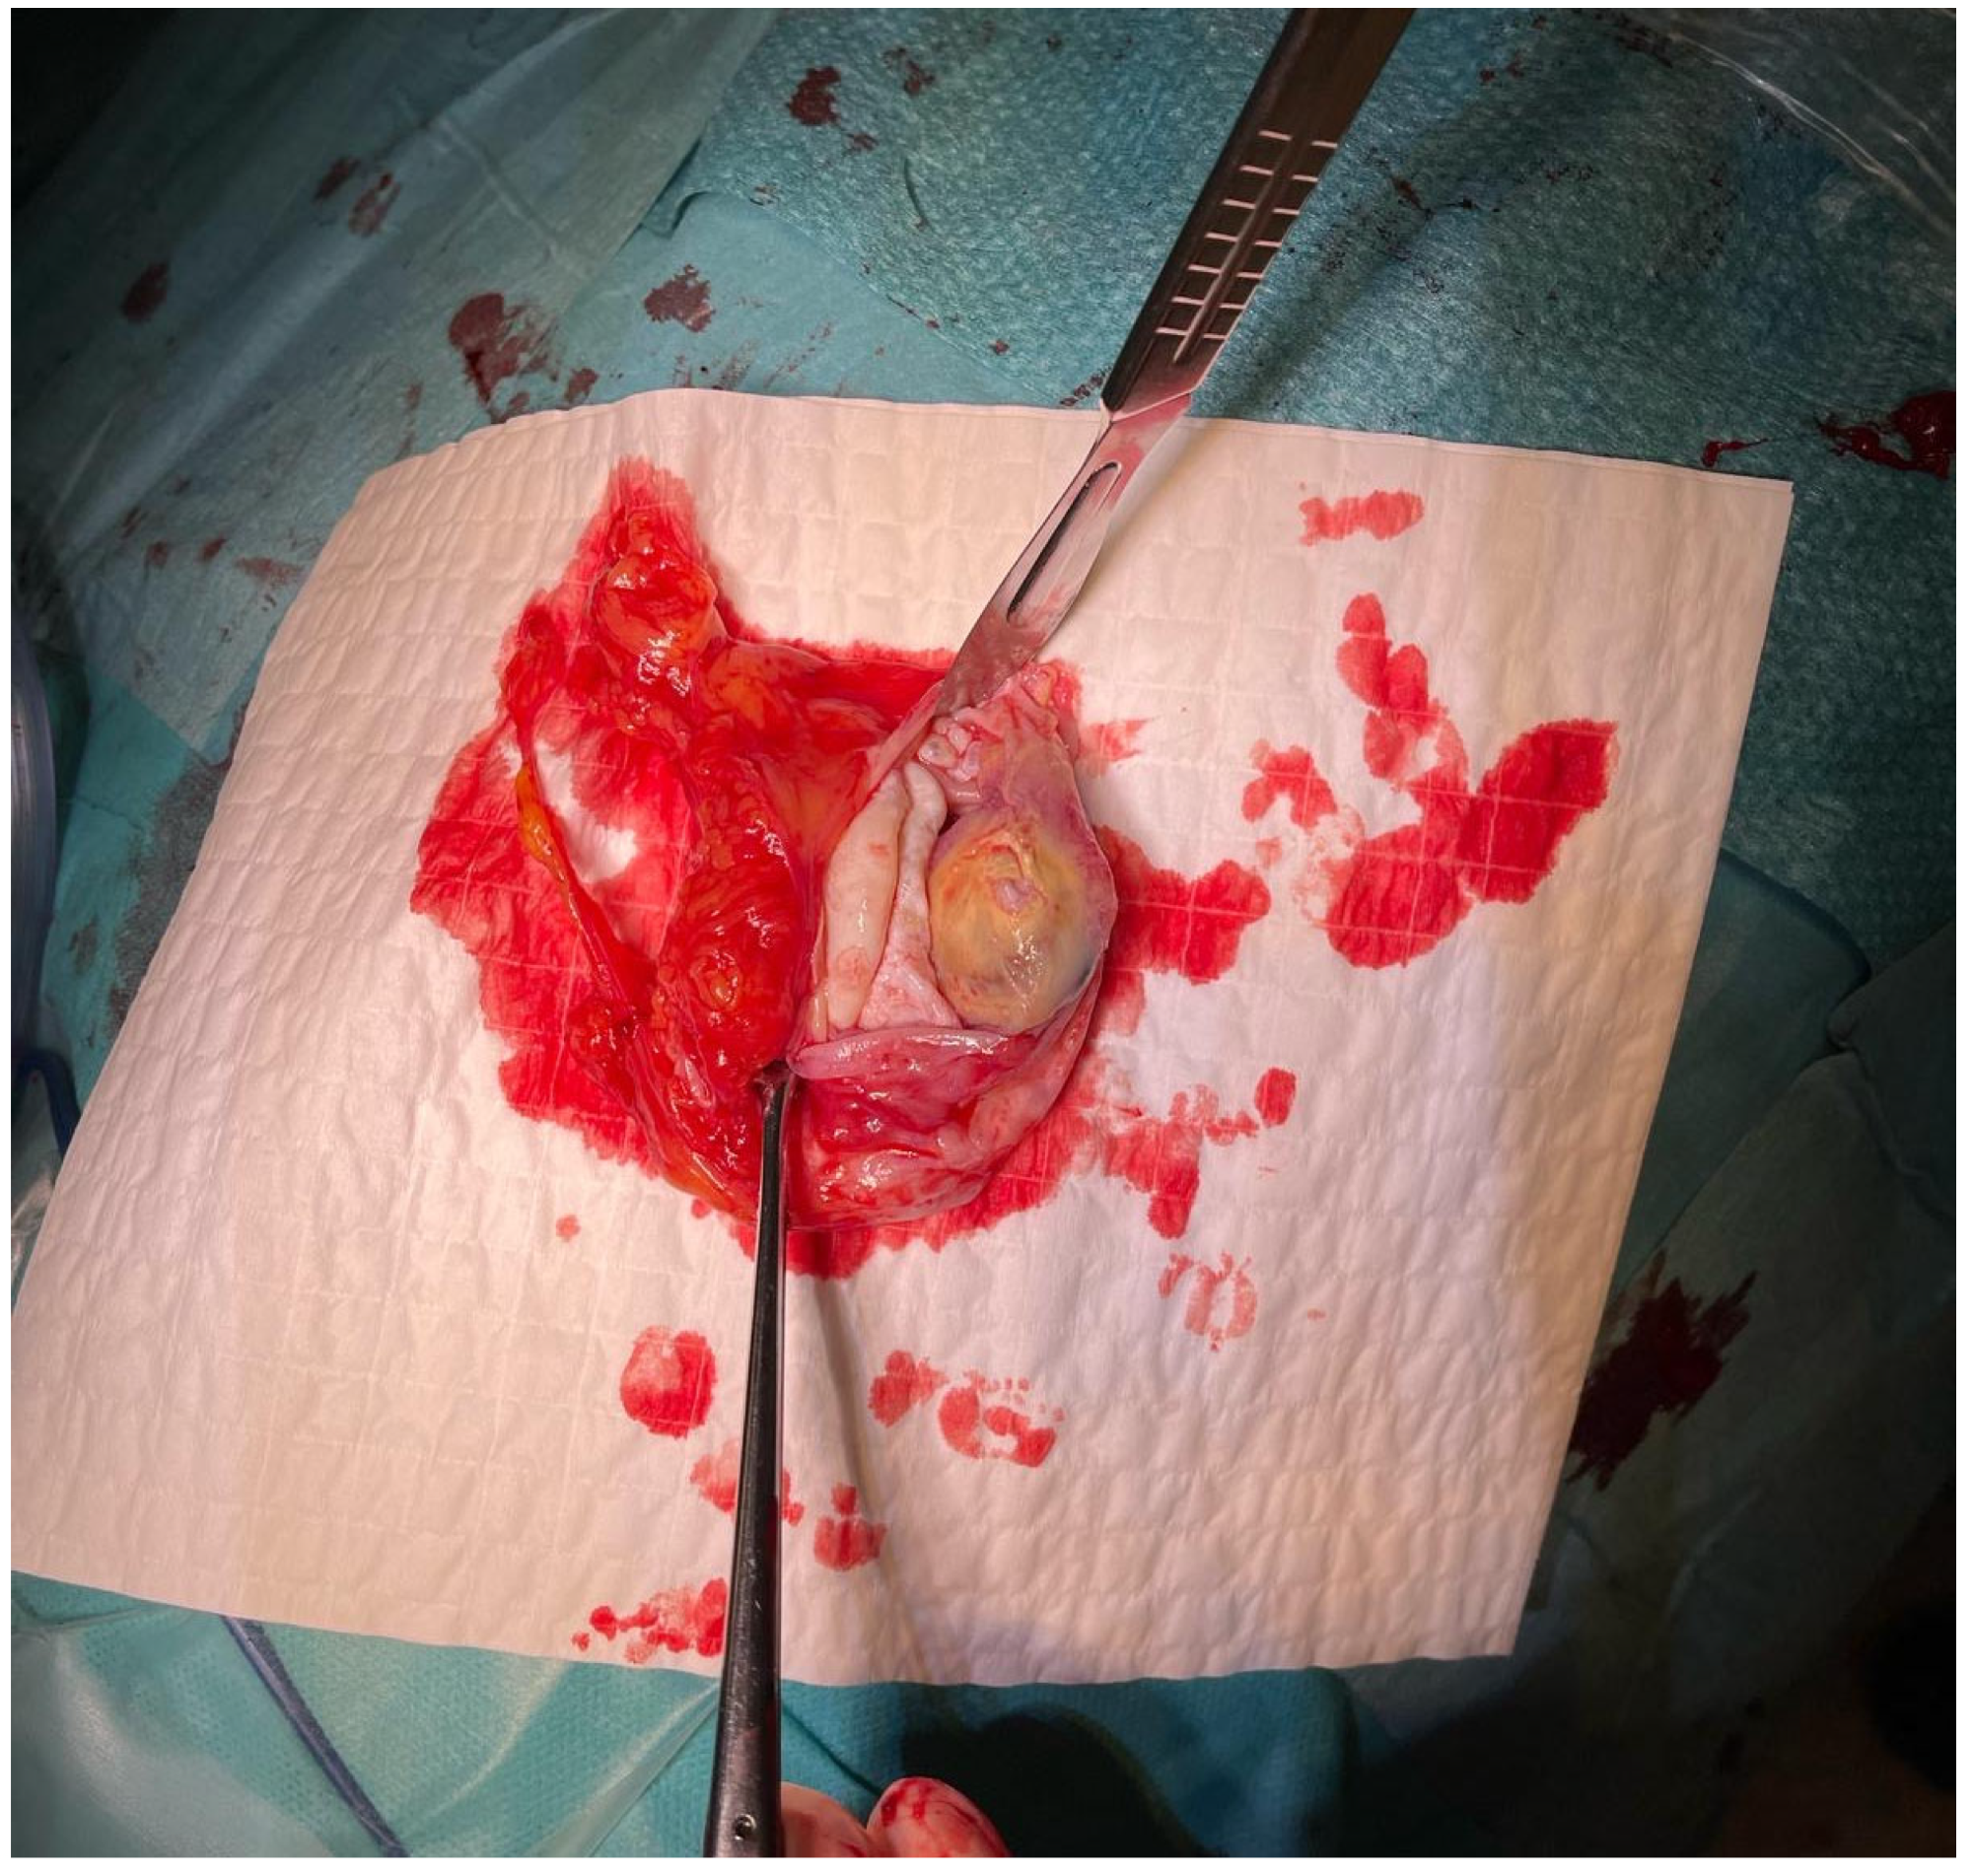

Due to the absence of medical contraindications, the patient was scheduled for elective surgical removal of the lesion. A thoracotomy was performed, with excision of the old scar and removal of the left fifth rib. The pleural cavity was obliterated, and a sharp detachment was performed within the upper lobe without interfering with the lower lobe. A thick-walled cyst measuring approximately 80 × 70 mm was visualized in the anterior mediastinum. This estimated visual dimension during thoracotomy, which is an approximate assessment, may be disturbed by the position of the cyst in the intraoperative field, hence the difference in relation to the dimensions from CT. This was the traditional surgical technique for mediastinal cystic lesions. The tissues were gently dissected and the lesion was enucleated using blunt dissection without rupturing the cyst wall. The operation had to be performed carefully so as not to rupture the cyst wall and cause contamination. After thorough examination, no focal lesions were found in the left lung.

The material was submitted to intraoperative examination (Figure 3). The cyst measured (ex vivo) 95 mm × 61 mm × 22 mm (Figure 4). The dimensions of the postoperative specimen are the ex vivo dimensions after removal and dissection of the cyst. The cyst flattened after fluid removal, explaining the difference in dimensions compared to the CT scan, which showed the cyst in situ, filled with fluid. Upon dissection, it had an uneven whitish internal surface with nodular thickening. Biopsies were collected for histological and cytological examination. The cyst fluid had not previously been aspirated for independent analysis. Cytological examination involved making a smear from the inner surface of the cyst wall, but only biopsies from the cyst wall, not from the nodular portion, were collected for histological examination. The cyst wall showed signs of necrosis and the presence of histiocytes and lymphoid cells. Cytological examination revealed structures consistent with protoscolex (Figure 5), suggesting Echinococcus spp.

Figure 3. Intraoperative image of the Echinoccocus spp. cyst removed from the patient’s anterior mediastinum.